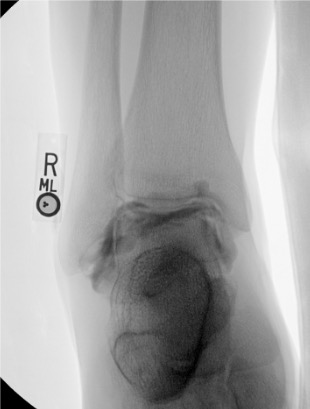

Ankle

Needle placementPost-injection